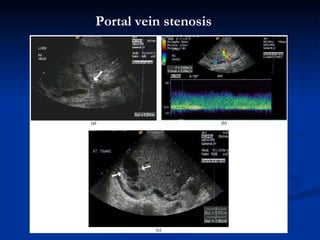

P ortal vein   stenosis

P ortal vein  thrombus